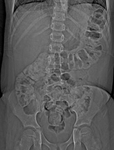

CT scan demonstrating faecalith (white arrow) outside the lumen of the appendix consistent with perforated appendix

From the collection of Dr KuoJen Tsao; used with permission